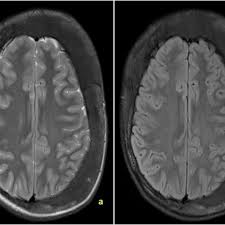

An enchondroma is a benign cartilage tumour found inside bones. Hemimegalencephaly is a rare congenital disorder of cortical formation with hamartomatous overgrowth of all or part of a cerebral hemisphere. Albright hereditary osteodystrophy pseudohypoparathyroidism a disorder involving the inability to respond to parathyroid hormone affecting bone growth and height Fibrous dysplasiaMcCune Albright syndrome a disorder that affects bones skin pigment and the endocrine system.

Enchondromas have a characteristic appearance on Magnetic Resonance Imaging MRI as well. Oral Surgery Oral Medicine Oral Pathology Oral Radiology is required for all clinicians involved in the diagnosis and treatment of oral and maxillofacial disease. GeneReviews an international point-of-care resource for busy clinicians provides clinically relevant and medically actionable information for inherited conditions in a standardized journal-style format covering diagnosis management and genetic counseling for patients and their families.